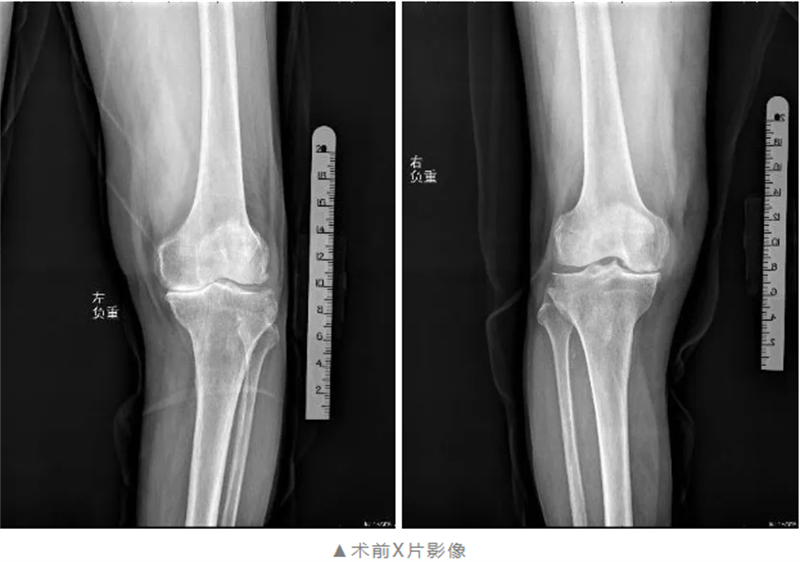

黃阿公的膝關節(jié)噩夢始于30年前,長期的膝關節(jié)疼痛逐漸導致他的雙腿變成嚴重的“O”型腿,每走一步都劇痛難忍。性格開朗的他不得不長期臥床,生活質量急轉直下,身心飽受煎熬。“看著父親被病痛折磨,我們卻束手無策,心里太難受了。”黃阿公的兒子回憶道。

經過全面細致的檢查與多學科會診評估,關節(jié)骨病科團隊在與黃阿公及其家屬充分溝通后,制定了個性化的膝關節(jié)手術方案——雙側膝關節(jié)單髁置換術,在膝關節(jié)磨損的部位植入特殊材料的“墊片”,最大限度的保留了患者的本體感覺和關節(jié)功能。